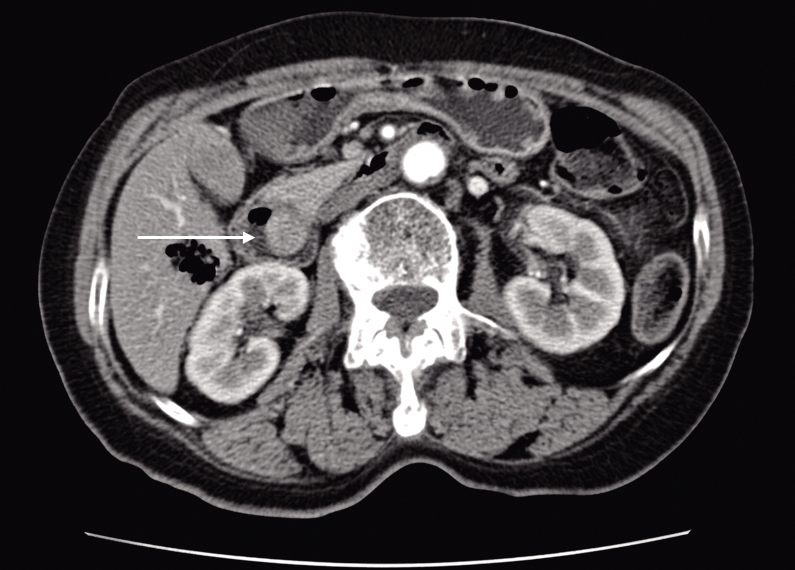

2026, 35(2):279-288. doi: 10.7659/j.issn.1005-6947.250625

摘要:背景与目的 Hem-o-lok夹广泛应用于腹腔镜胆囊切除术(LC)中的胆囊管及血管闭合,但其术后移位虽罕见,却可进入胆总管形成异物,影像学表现易误诊为胆总管结石,增加诊断与治疗难度。针对该远期并发症的识别与处理,临床认知仍有不足。本文通过分析1例相关病例并结合文献复习,总结其临床特征及诊治要点。方法 回顾性分析中国人民解放军空军军医大学第二附属医院普通外科2025年10月收治的1例29岁女性患者的临床资料。患者4年前行LC,本次因体检发现“胆总管结石”1年余入院,术前影像学提示胆总管多发充盈缺损。患者拒绝内镜下逆行胰胆管造影治疗,遂行腹腔镜胆总管探查术(LCBDE),术中确诊为Hem-o-lok夹移位。分析其诊疗过程、影像学特征及术中所见,并结合文献进行讨论。结果 术前影像学提示胆总管多发结石。LCBDE术中经胆道镜探查,于胆总管中下段取出3枚移位的Hem-o-lok夹,周围未见胆色素结石,确诊为“胆总管异物(Hem-o-lok夹)”。术后置T管引流,恢复顺利出院。术后2个月T管窦道造影示胆总管通畅,无残留异物或结石,顺利拔管。结论 Hem-o-lok夹移位是LC术后一种罕见的远期并发症,影像学易误诊为胆总管结石。对有相关手术史的患者,应将其纳入鉴别诊断。LCBDE是确诊及处理该并发症的有效方式。规范术中操作及合理选择闭合方式,并加强术后随访,有助于降低此类并发症风险。